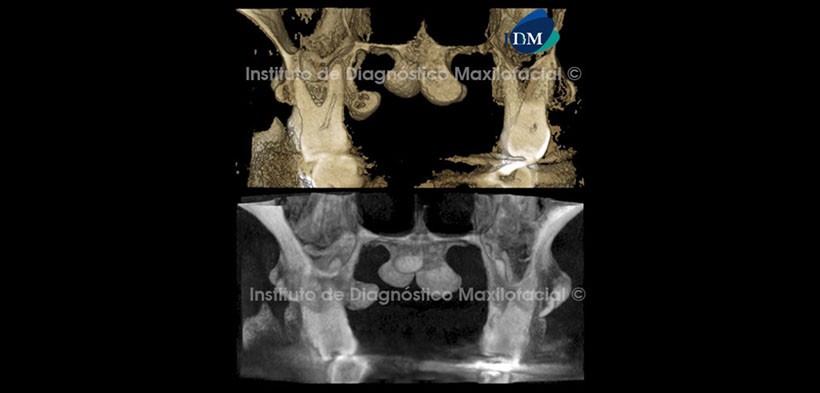

Así mismo, el software Romexis nos brinda diferentes opciones de reconstrucción 3D, como por ejemplo la opción radiográfico matizado que nos muestra preponderantemente las estructuras con alto contenido mineral como el tejido óseo. También tenemos la opción radiográfico que nos ilustra la zona de estudio en escala de grises, la cual complementa de manera ideal la opción anteriormente descrita (Fig. 4, 5 y 6).